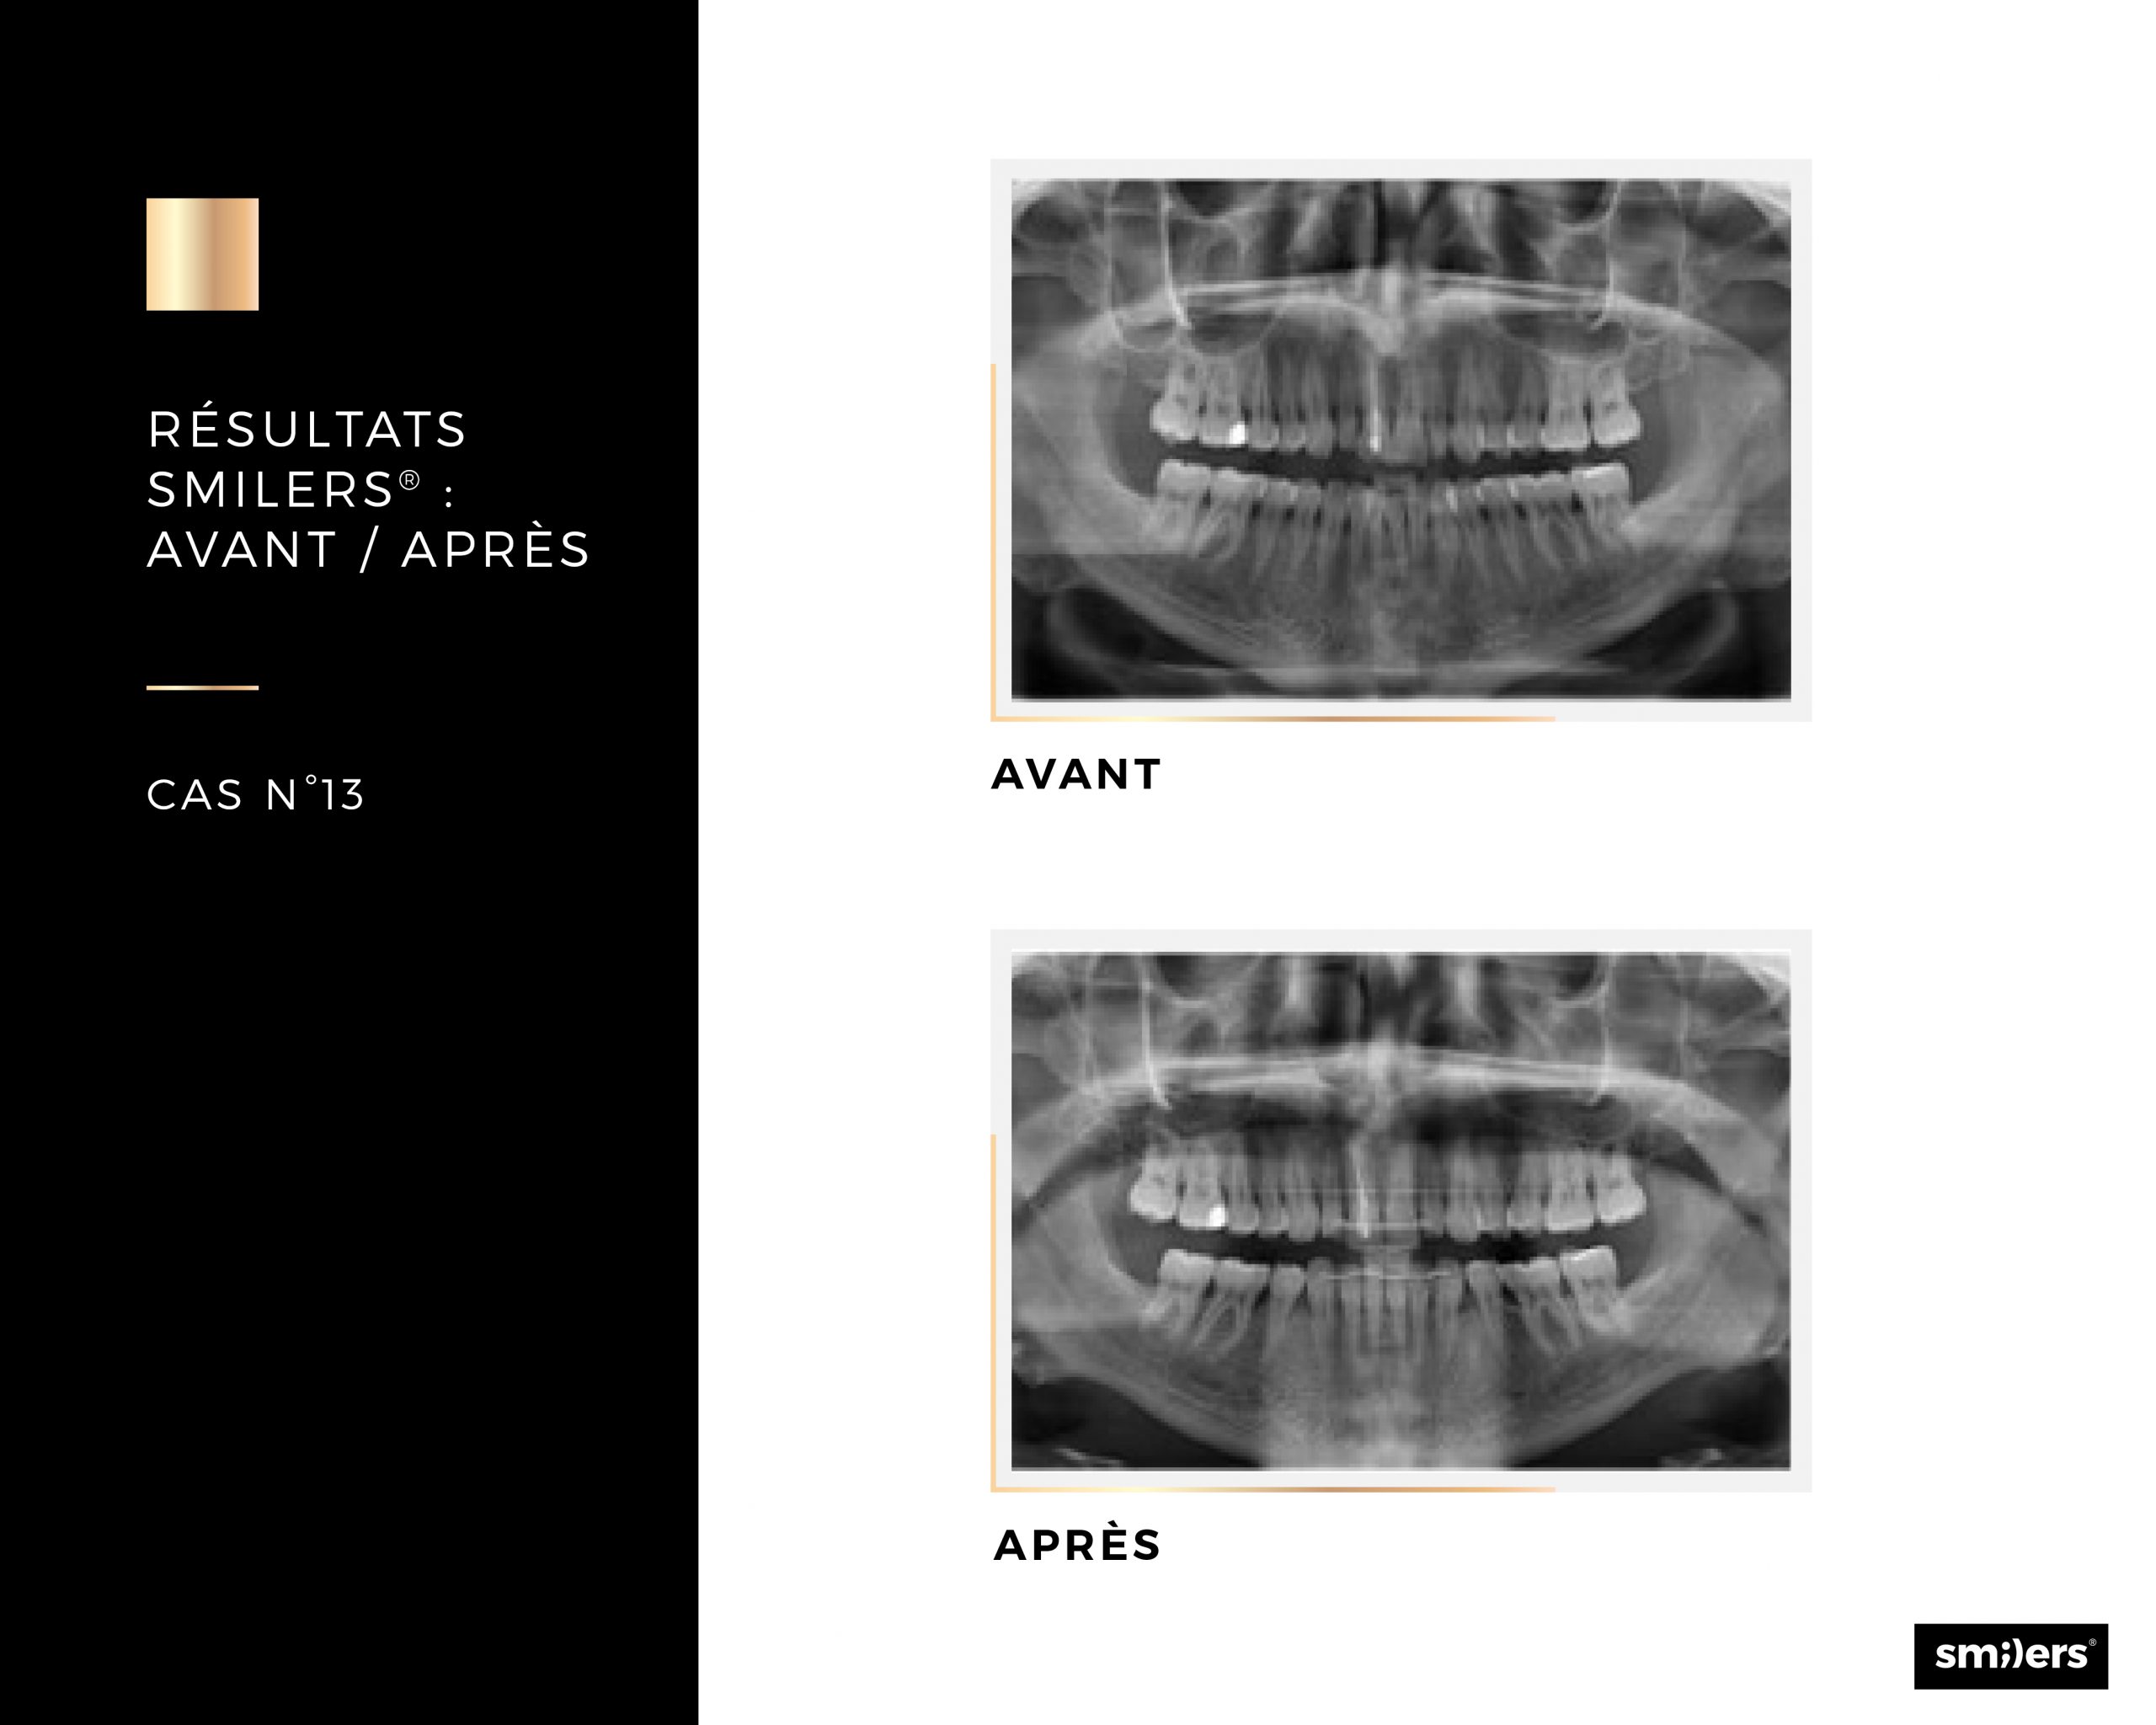

- L’usage de gouttière orthodontique Smilers® peut aussi être envisagé avant de faire certains traitements dentaires (par exemple la pose d’implants)